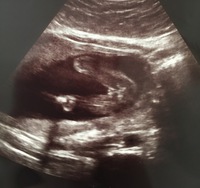

18 週 性別 女の子 エコー-妊娠18週目エコー写真・赤ちゃんの大きさ・胎動が分かる人も 妊娠18週目(18w)のエコー写真を見てみると、胎児の大きさはCRL(頭殿長)が13cm~14cm、体重は150gほどに成長、神経回路が発達する時期です。 妊娠十八週は、個人差がありますが、胎動や赤ちゃんの性別が分かる人も出てきます。 母体は、お腹も膨らみ、丸みを帯びた体形となっていくので、腰痛に注意が 妊娠26週目のエコー写真 お腹の赤ちゃんの性別が判明! 紛れもなく男の子のシンボルですよね! 先生が言う前に「先生、ついていますよね、これ」と私が言うほどに一瞬でわかりました。

妊娠週 18w3d 4週間ぶりのエコー検査、顔がはっきり見えてびっくり! どことなく旦那にのような。 性別判定はまだだと思っていたのに男の子と判明しました! おなまえ ぐぐ ねんれい 29 妊娠週 18w3d 1ヶ月ぶりのエコー 前は全身写ってたのに、もう腰から上しか写ってなくて成長に驚き (^^) お腹がぽっこりでかわいい (^^) ストレスを感じた1ヶ月でしたが、先生に 10年7月18日 0612 2人とも同じ総合病院ですが、27~28週のエコー技師診察までは性別は教えてくれません。 今は31週で22週の頃に女の子って 身体のバランスは3~4頭身になり、頭には髪の毛が生えてきて顔にも脂肪がつき始めるので、より赤ちゃんらしいかわいい顔つきになってきます。 出典: featurecozrejp 妊娠18週になると、より赤ちゃんらしい体つき、顔つきになり、エコー写真でもそんなかわいい様子が見られます。 超音波検査でおまたがバッチリと写り、性別がわかった! という声も聞かれます

妊娠週 18w0d 1ヵ月ぶりのエコーは、大きくなっていて画面に入らなくなっていて、驚きました♪週数通りの250g程みたいです。 足をしっかり挙げてVの字になっていて笑ってしまいました。 先生には「性別は次の検診の時かなぁ」って言われたけど、エコーの股の間には丸いものが見えたので、もしかして男の子かなぁと夫婦で推察しています。 おなまえ 楓 ねん男の子女の子別 妊娠18週、性別は女の子に判明!エコー画像を大 女の子と性別が確定するのは妊娠7ヶ月以降!エ 妊娠19週目(19w1d~6d)のエコー写真とエピ エコー写真で性別はいつ判明?男の子と女の子の 妊娠19週目 胎動や性別が分かる人も!妊娠18週、性別は女の子に判明!エコー画像を大公開 生まれてくるまでわからない!エコー検査で性別の間違いって 妊娠17週目!女の子の性別もわかる?おむつのムーニー 公式 男の子のエコー写真の特徴とは?女の子との違いや性

妊娠 性別。女の子はいつくらいに確定しましたか? 7ヶ月に入ったばかりの二人目妊婦です。 一人目の時と同じ総合病院に通っているのですが、エコーは産むまでに3回しかしてくれません。しかも2Dです^^ 質問No 赤ちゃんの様子をエコーで見てみた②~性別は女の子? ? 妊娠18週目~ きのうに引き続き、検査技師さんにエコーで赤ちゃんを見てもらった記事のつづきです😊 前回の 記事 『赤ちゃんの様子をエコーで見てみた①~低置胎盤? ~』 きのうの記事では、赤ちゃんに先天性の異常はなさそうだということは分かりました でも、「胎盤が少し低い位置にある」と 妊娠18週、性別は女の子に判明! エコー画像を大公開! 妊娠18週のエコーで、私たちの赤ちゃんは女の子だということがわかりました! その鮮明なエコー写真を見て、「あ~、これが女の子なんだ~」と納得。 多くのエコー検査では「99%は確実」と言われていますが、まれに生まれてきて性別が違うこともありますよね。 でも今回の場合は、ドクターも「100